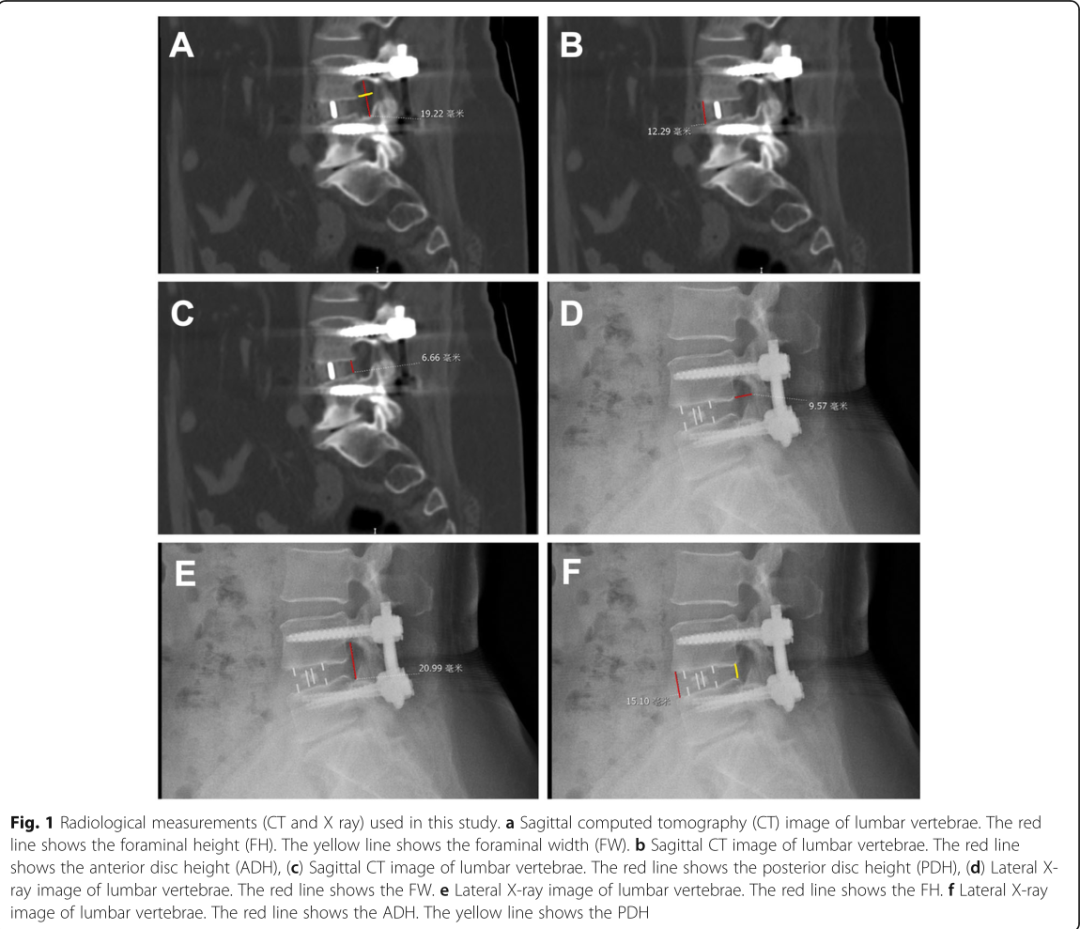

斜位侧方椎间融合术(OLIF)是由侧方腰椎间融合术(LLIF)和前路腰椎间融合术(ALIF)发展而来的一种手术技术。相对于LLIF,OLIF的优势在于较大的侧向融合器可实现更高的融合率和角度校正。与开放式手术相比,这种手术方法减轻了手术后的背部疼痛,缩短了手术时间和住院时间,还减少了出血。为了比较独立的斜外侧腰椎融合术(OLIF)与OLIF联合后路双侧经皮椎弓根螺钉固定术(OLIF联合)治疗腰椎滑脱症的效果。来自北京积水潭医院的WEI HE 教授及上海长征医院的Jiankun Wen教授及其团队进行了一项回顾性研究,其结果发表在2020年的BMC MUSCULOSKELETAL DISORDERS杂志上。

作者分析了2014年至2017年在北京积水潭医院(联合OLIF组)和上海长征医院(单独OLIF)行单独OLIF或OLIF联合后路双侧经皮椎弓根螺钉固定术(联合OLIF组)的患者组。其中联合OLIF组有41例,单独OLIF组有32例。研究人员收集病人术前信息,手术详情,并在术后6、12个月对其进行CT等检查,由独立两组的医生对结果进行评价。

随访2年,VAS和ODI评分无差异,但独立OLIF在1周和3个月时评分更好(P <0.05)。与独立的OLIF组相比,手术前和手术后OLIF组的PDH和FW较小(all P <0.05)。两组之间在术前,第1周和第3个月时的FH有显着差异(all P <0.05),但在第2年时差异消失(P =0.111)。